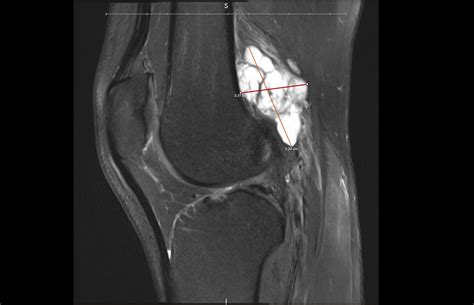

MRI (Magnetic Resonance Imaging) Provides detailed images to ensure the cyst isn't connected to a tumor or deep ligament tear.